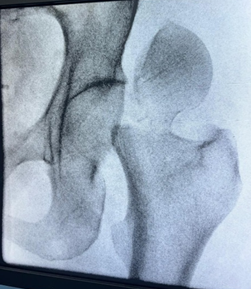

Salvaging Femur Head in a Pipkin Type III Femoral Head Fracture with Open Reduction and Internal Fixation Using Herbert Screw Fixation: A Rare Case Report

Mohammed Amjad Sohiel , Santosh D Ghoti , Ajit S Rathod , Jaideep Das , Aditya A Agarwal , Akshay Punekar

………………………………p.89-94